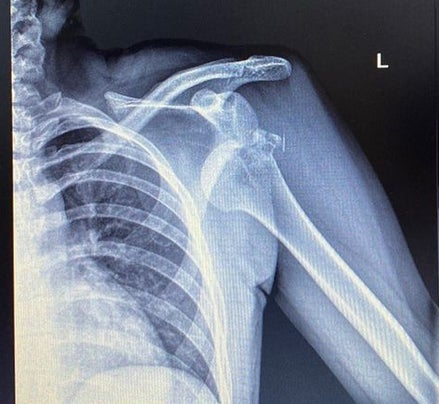

Gebrochen und ausgekugelt! Das Röntgenbild nach dem Sturz von ÖSV-Dame Marie-Therese Sporer.

© Instagram/@mariesporer